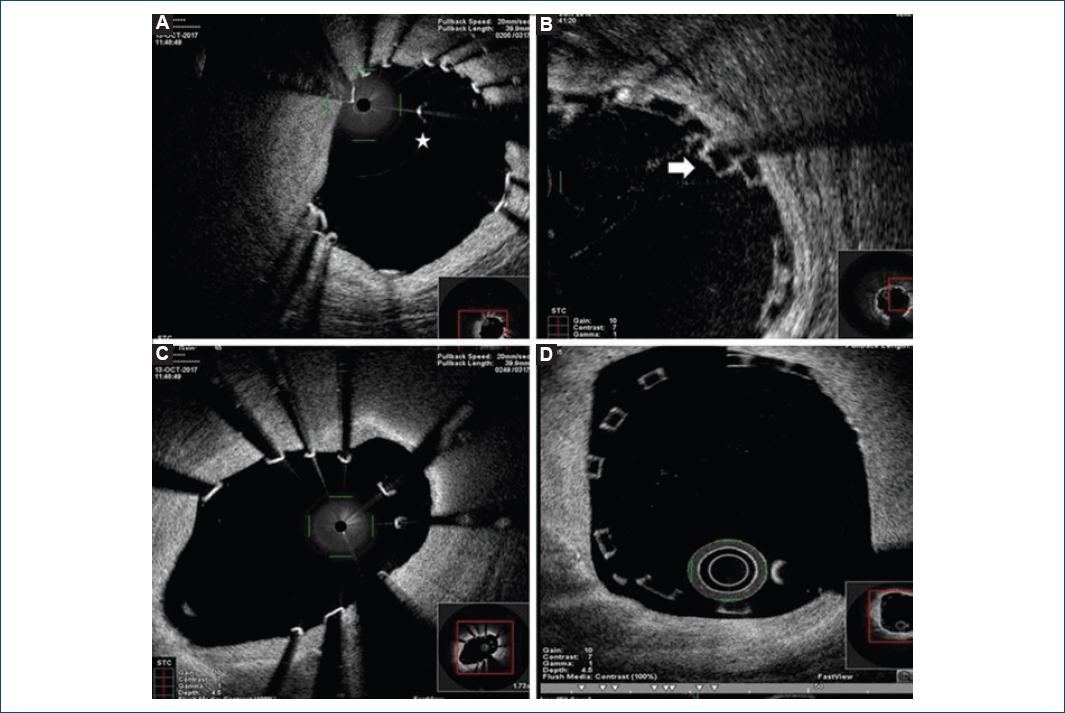

In addition to this, Magmaris® greater percentage of elongation-at-break had been hypothesized attending to mechanical properties of magnesium alloy11. Nevertheless, no clinical evidence was available. We evaluated for the first time in vivo acute scaffold disruption of Magmaris® device by OCT intracoronary imaging (Fig. 1). The percentage of disrupted struts in Magmaris® group was minimal and significantly lower than in the Absorb® group (0.15% vs. 0.27%, p = 0.03). These results confirm metallic BRS higher resistance to rupture, even when postdilatated at higher pressure levels (18.01 ± 2.15 vs. 17.20 ± 3.80 atm, p = 0.05).

Figure 1 Optical coherence tomography (OCT) in vivo evaluation of Magmaris® and Absorb® scaffolds disruption and malapposition. 1A and 1B: show different OCT intracoronary images of disrupted struts: the star points to a magnesium isolated strut and the arrow a stacked polymeric disrupted strut. Meanwhile, images 1C and 1D show metallic (1C) and polymeric (1D) bioresorbable scaffolds malapposition.

Main concern about polymeric scaffolds comes from their original slightly higher rates of ST when comparing to second-generation DES12,13. Nevertheless, the application of the PSP strategy (including high-pressure postdilatation) has demonstrated a significant reduction in ST and MACE rates after BVS scaffolding with the Absorb® device14,15, with no higher rates of acute scaffold disruption4. In line with this, we decided to perform and evaluate high-pressure postdilatation per protocol in all lesions treated with Magmaris® in our cath lab. We confirmed that a greater percentage of elongation-at-break allowed the operator to reduce Magmaris® malapposition rates in a safe manner (1.06% vs. 1.46 %, p = 0.01 of malapposed struts in Magmaris® and Absorb® groups, respectively). Even though Magmaris® device has been suggested to have lower acute thrombogenicity16 with no reported cases of ST6,17,18, it is well known that malapposition and infraexpansion significantly increase the risk of scaffold thrombosis and restenosis. According to this, we support the use of high-pressure postdilatation after magnesium-scaffold deployment to optimize angiographic and secondary clinical results, specially avoiding scaffold malapposition (Fig. 1).